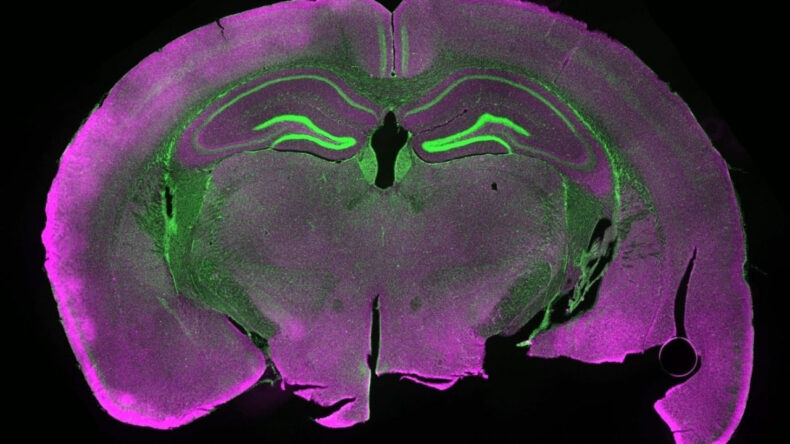

Fare beyin dokusunu dondurdular, ortaya çıkan sonuç şaşırttı

Almanya'da yapılan yeni bir bilimsel araştırma, beyin dokusunun aşırı düşük sıcaklıklarda dondurulup çözdürüldüğünde yeniden hayata döndürülebileceğini ortaya koydu.

Proceedings of the National Academy of Sciences dergisinde yayınlanan çalışmaya göre araştırmacılar, beyin dokusunu -196 dereceye kadar dondurup yeniden çözme işleminde nöronların işlevsel bağlantılarını büyük ölçüde koruyabildiğini gösterdi.

Daha sonra da fare beyninden alınan hipokampüs dilimleri sıvı nitrojende -196 dereceye kadar soğutuldu. Doku tekrar ısıtılırken hücrelerin şişmesini ve çatlamasını önlemek için ise özel bir kimyasal “antifriz” solüsyonu kullanıldı.

Mikroskop altında yapılan incelemelerde nöronlar arasındaki sinaptik bağlantıların büyük ölçüde korunduğu, hücrelerin enerji üretim merkezi olan mitokondrilerin yeniden aktifleştiği, elektriksel uyarı verilen nöronların ise tekrar sinyal üretebildiği saptandı.